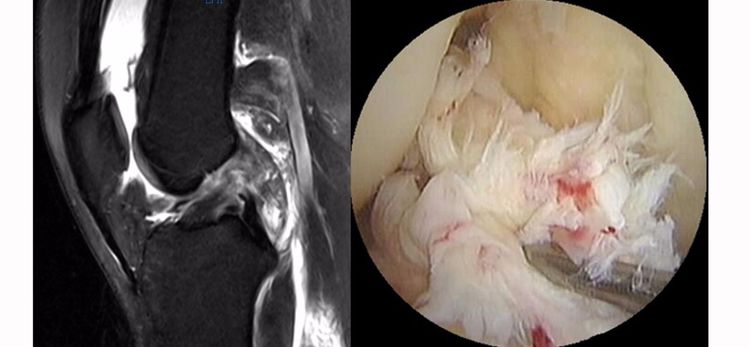

ACL损伤的间接征象:指ACL断裂后胫骨前移位出现的一系列改变。间接征象只能考虑可能有ACL损伤。

1.骨挫伤(轴移征):一旦ACL撕裂,胫骨就相对于股骨前移,使股骨外侧髁和胫骨外后方撞击,双方均出现水肿,而且膝关节屈曲的程度决定股骨髁挫伤的部位。

2.沟槽征:当股骨外髁骨因撞击造成的凹陷深度>2mm时称为沟槽征,代表受到撞击的暴力更大。

3.接吻征:膝关节过伸受伤时,胫骨前部撞击股骨髁前部,形成对称性骨挫伤;如果同时有一外翻力的话,膝关节外侧可出现对称性挫伤,这种对称性骨挫伤称为接吻征。也有人把轴移造成的股骨外侧髁和胫骨外后方水肿称为接吻征。